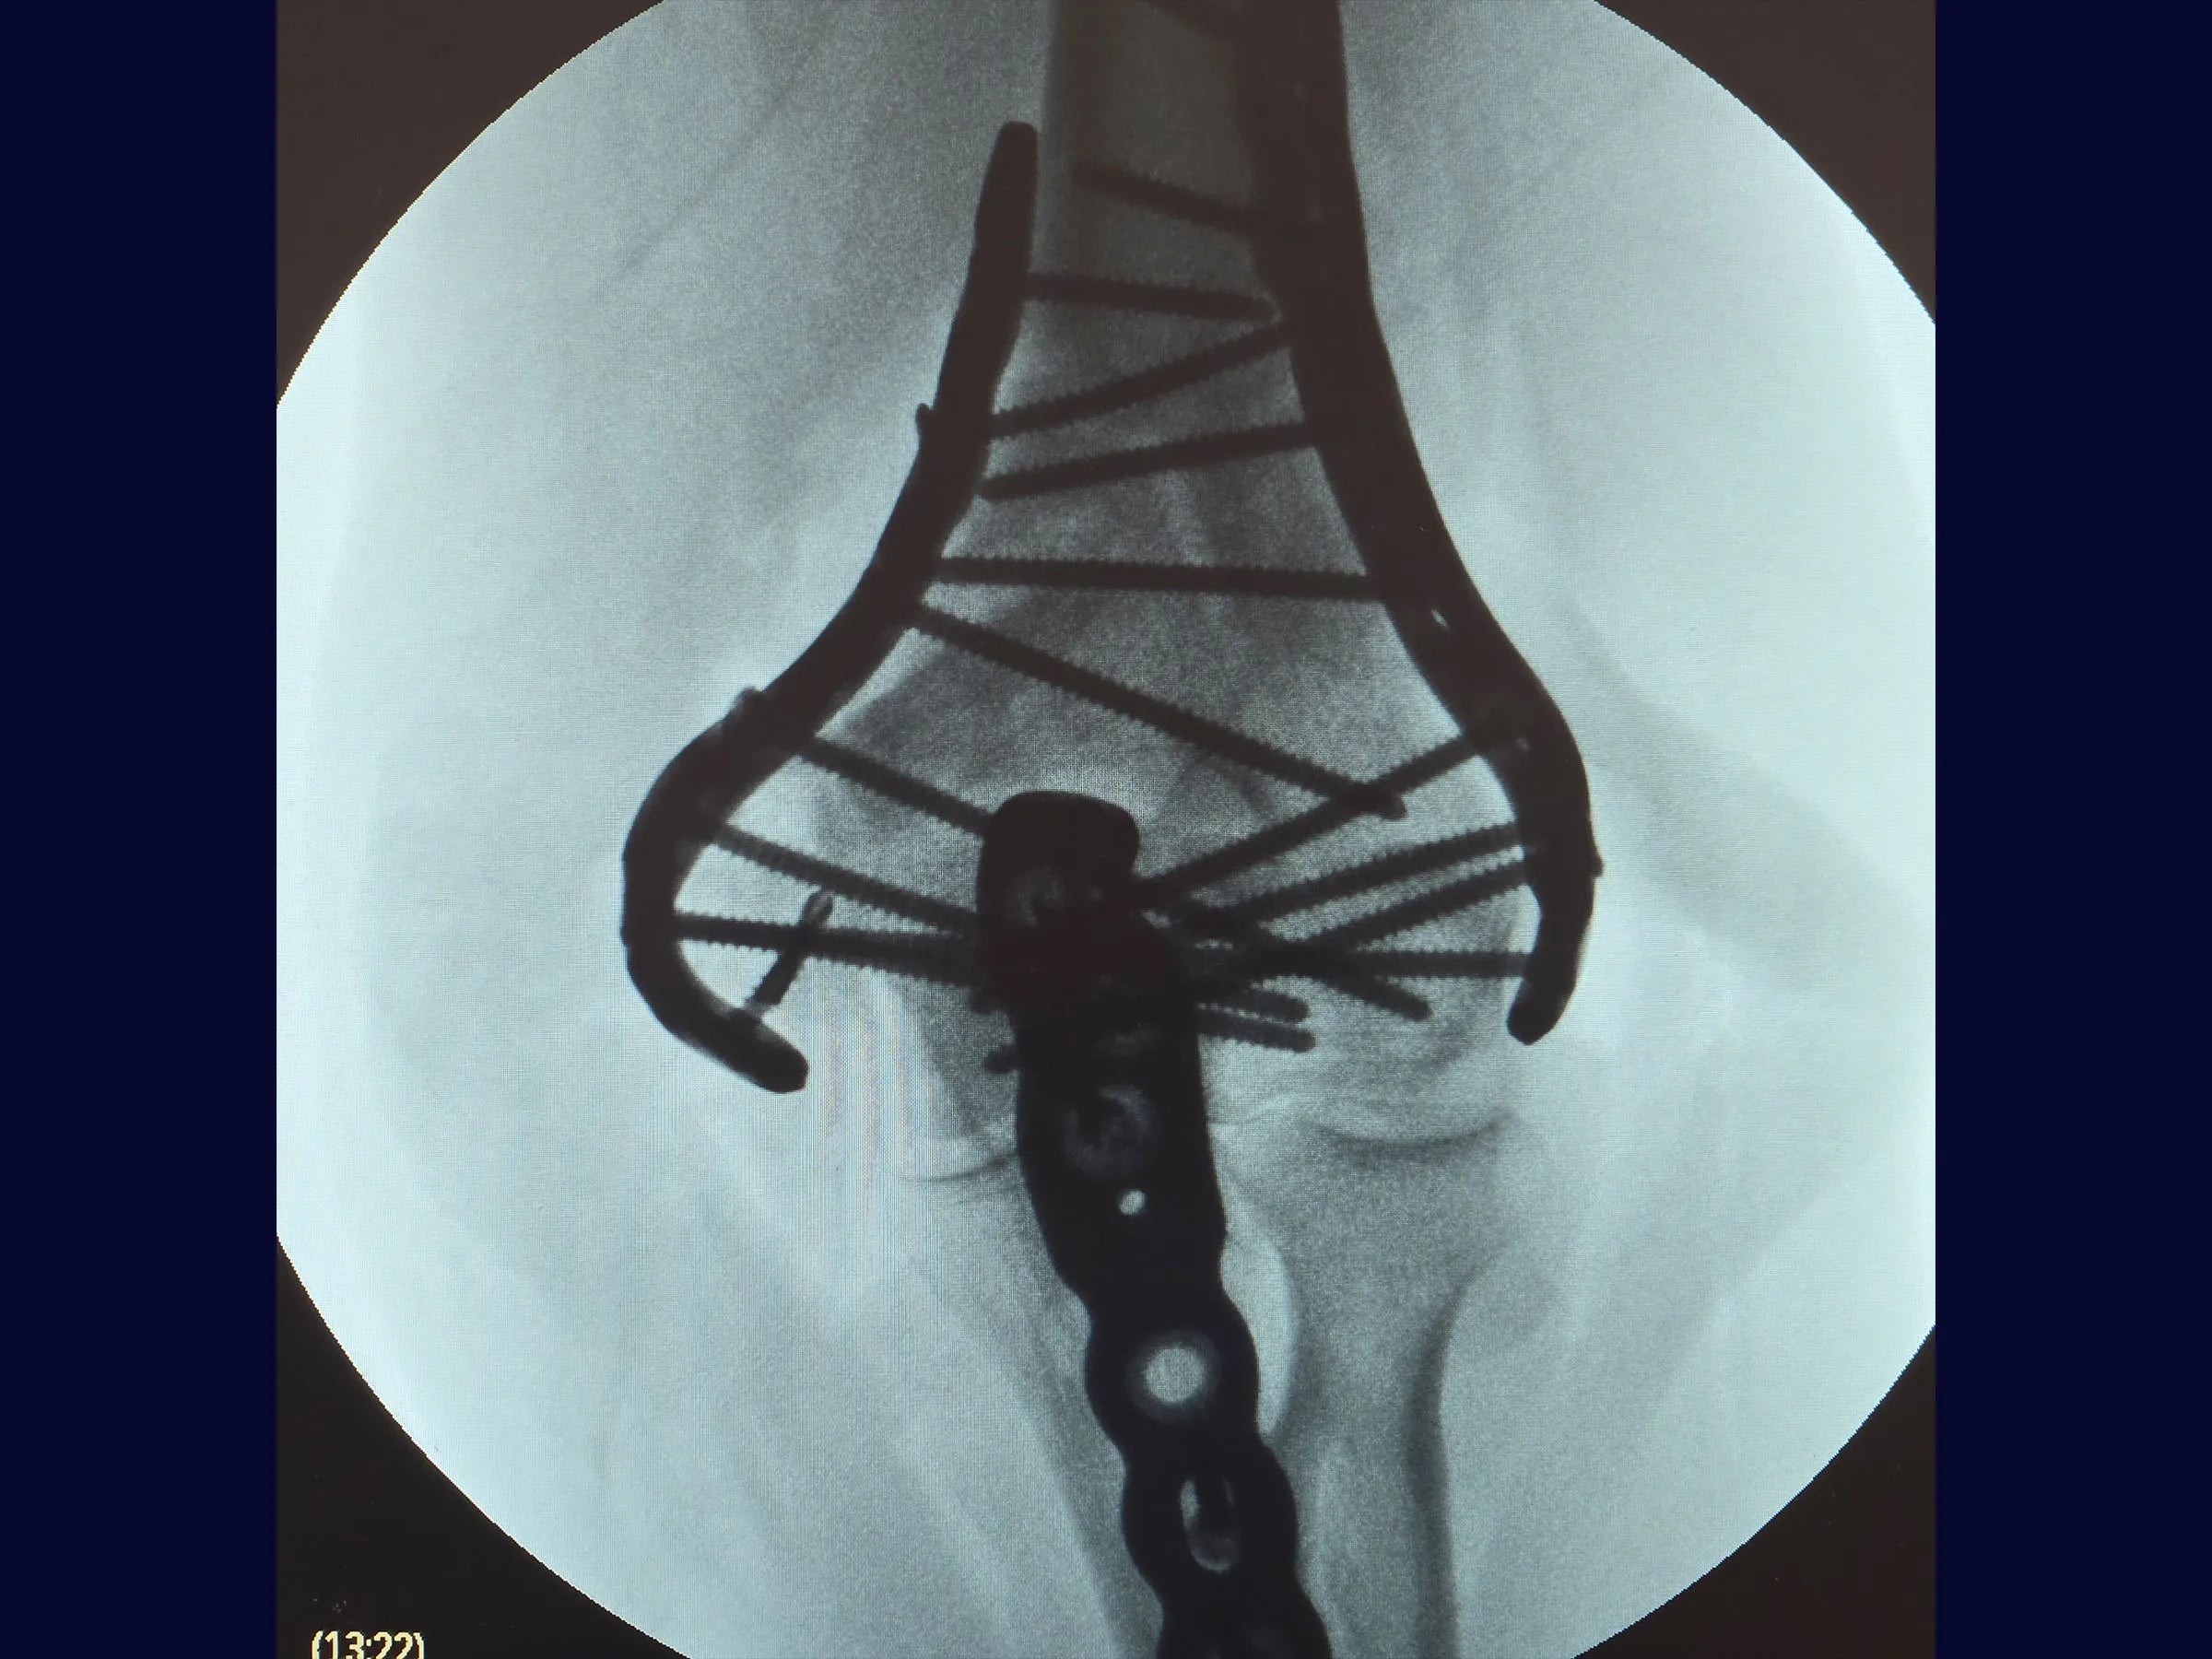

As fraturas articulares multifragmentares do úmero distal representam um dos maiores desafios na cirurgia do trauma, exigindo precisão na redução articular e estabilidade que permita mobilização precoce.

Este treinamento oferece uma visão detalhada da fixação rígida com placas de ângulo variável, apresentada em vídeo 4K sob a perspectiva cirúrgica, com comentários técnicos e material complementar em PDF.

- Osteotomia em Chevron no olécrano para ampla exposição articular.

- Redução de fragmentos articulares com fios de Kirschner em joystick.

- Fixação definitiva com placas bloqueadas de ângulo variável.

- Redução Controlada: Uso de fios K como joystick para manipulação de fragmentos articulares e restauração das colunas.

- Fixação Estável: Aplicação de placas bloqueadas de ângulo variável para alinhamento seguro e resistência biomecânica.